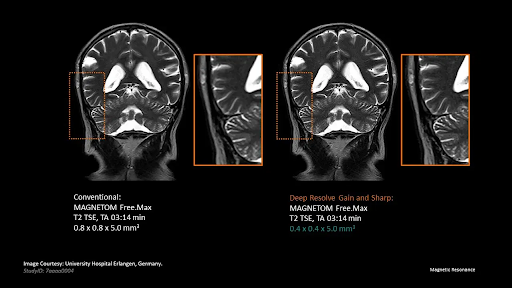

Siemens Deep Resolve AI leverages advanced artificial intelligence, specifically convolutional neural networks, to accelerate MR scans beyond previous capabilities. This AI-powered image reconstruction technology speeds up the scanning process and delivers sharper, more precise images. Integrating Deep Resolve Sharp and Deep Resolve Gain technologies allows for enhanced image clarity, making it possible to achieve high-resolution images from low-resolution input, all while maintaining the integrity of the raw data collected during the scan.

At the core of improving image quality is the Siemens Deep Resolve Sharp technology, which utilizes a deep neural network trained on extensive datasets of high and low-resolution MR images. This allows it to reconstruct high-resolution images from lesser-quality inputs. The benefits are manifold: increased image sharpness, faster image acquisition without sacrificing quality, and the ability to depict small structures more clearly than ever. It combines the power of supervised learning with in-depth knowledge of MRI physics to deliver exceptional performance and reliability.

Deep Resolve Gain is an advanced image reconstruction technology that intelligently reduces noise. Using individual noise maps, it precisely addresses local noise variations, significantly improving the signal-to-noise ratio (SNR). Fully compatible with TSE sequences, it offers reliability and versatility in clinical applications.

Deep Resolve Sharp is an advanced image reconstruction technology that enhances sharpness with exceptional precision. Using a neural network that is trained on paired low- and high-resolution images, it transforms input that may be of lower quality into high-resolution output.

It is different from traditional methods for interpolation that fill k-space gaps with zeros. This technology predicts and reconstructs data from distant k-space regions for superior clarity. Crucially, the original raw data stays integral to ensure accuracy and reliability in the final output.